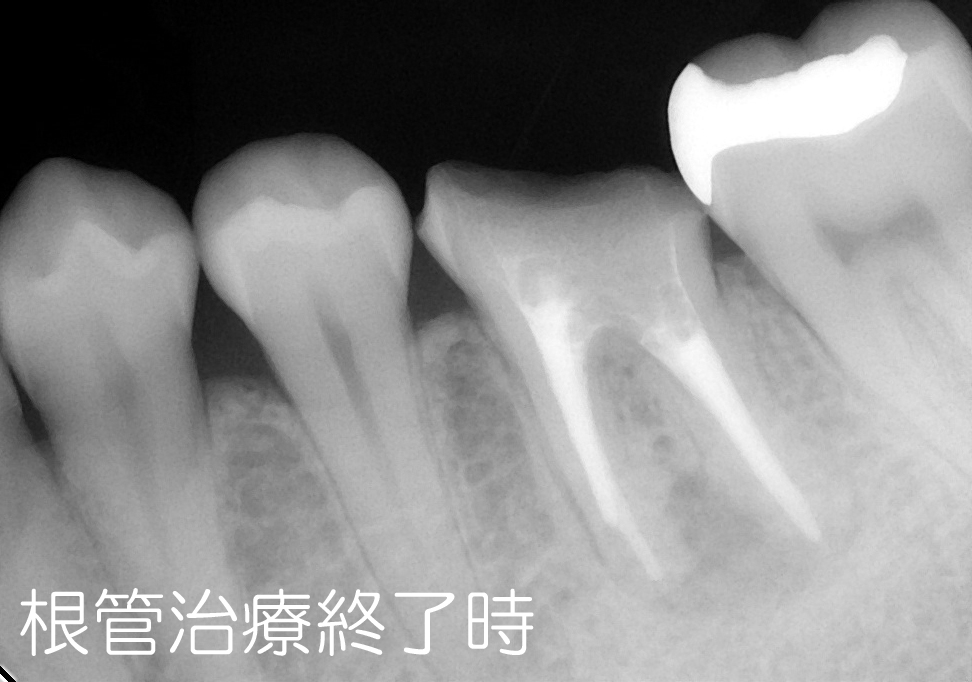

そして、9年後がこちら

現在まで良い状態を保っていただいております。

この9年間、症状が出たことはなく、快調だとのこと(^0^)/

治療の仕方については、9年前と現在を比較していろいろ思うところはありますが、それは別として現在までしっかりと機能して存在してくれていることは、患者さんの予防の意識が高くしっかりとセルフケアと我々のプロケアを欠かさずしてくれていることだと思います。

そして、私自身未熟ながらもマイクロスコープの能力を最大限発揮させるべく汗をかいた証なのかなと手前味噌ながら思います。